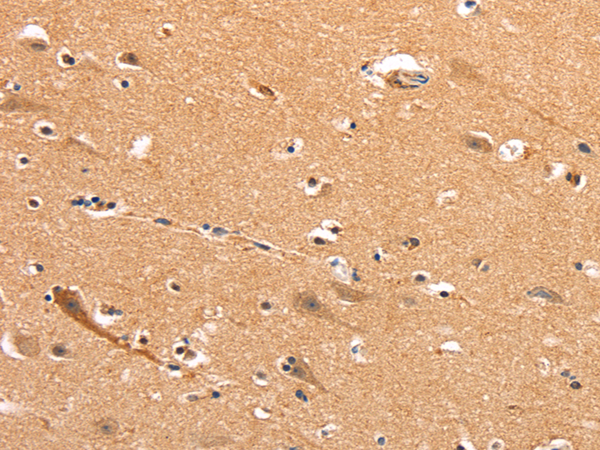

IHC positive control: |

Human thyroid cancer and Human brain |

IHC Recommend dilution: |

50-200 |